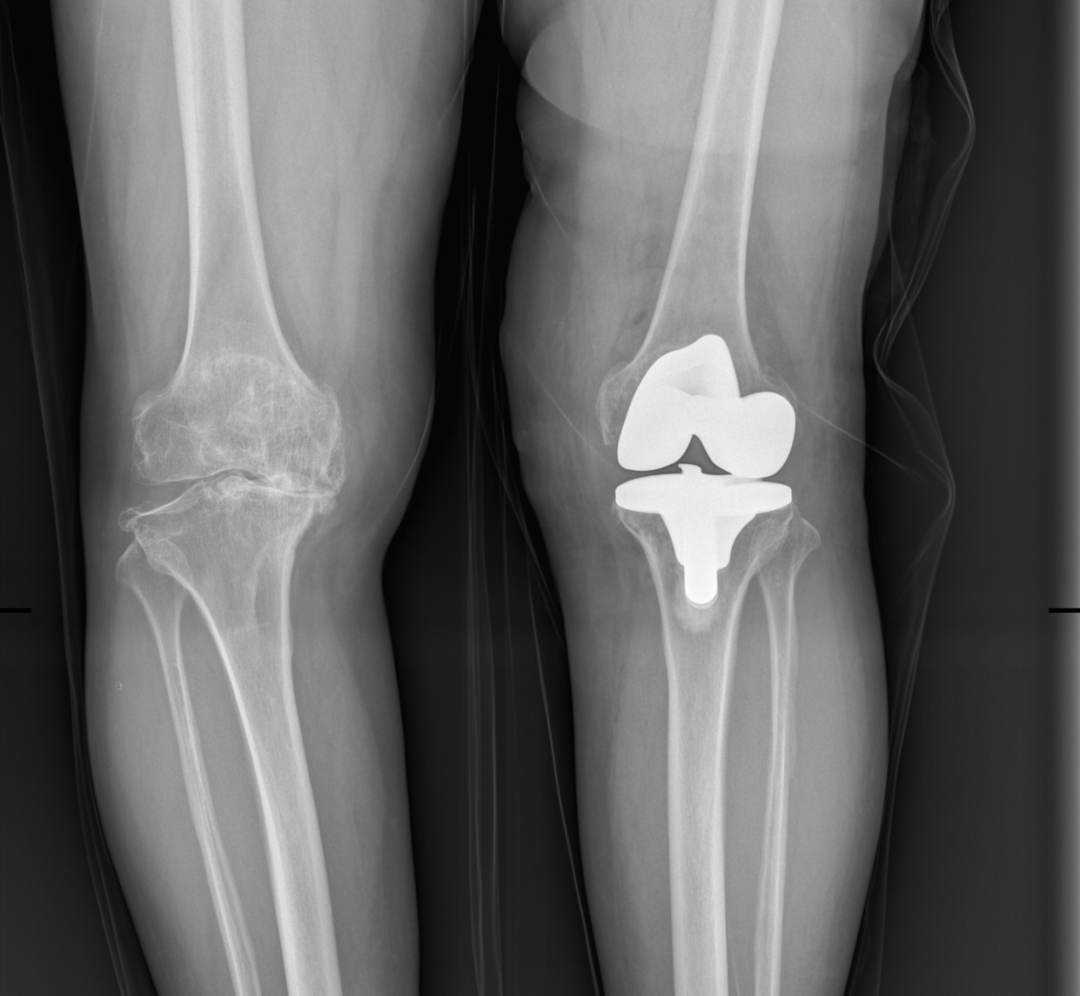

第一次左侧人工全膝关节置换术后